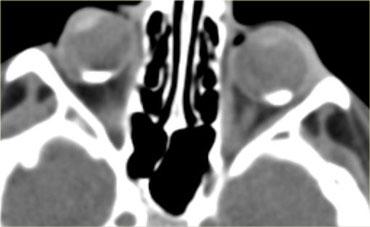

Hình bên trái là hình ảnh CT của một bệnh nhân bị chấn thương mắt trái.

Hãy phân tích hình ảnh để tìm 5 dấu hiệu trước khi tiếp tục đọc.

Các dấu hiệu bao gồm:

- Tiền phòng nông hơn so với bên phải, gợi ý vỡ nhãn cầu.

- Tỷ trọng trong tiền phòng tăng, gợi ý xuất huyết tiền phòng (hyphema).

- Tỷ trọng của thủy tinh thể giảm, cho thấy bệnh nhân bị đục thủy tinh thể do chấn thương.

- Có vùng tăng tỷ trọng trong buồng dịch kính, gợi ý xuất huyết dịch kính.

- Nhãn cầu dẹt ở mặt sau, cho thấy có vỡ dịch kính kèm theo.

Vỡ nhãn cầu thường gặp nhất ở vị trí tiền phòng.